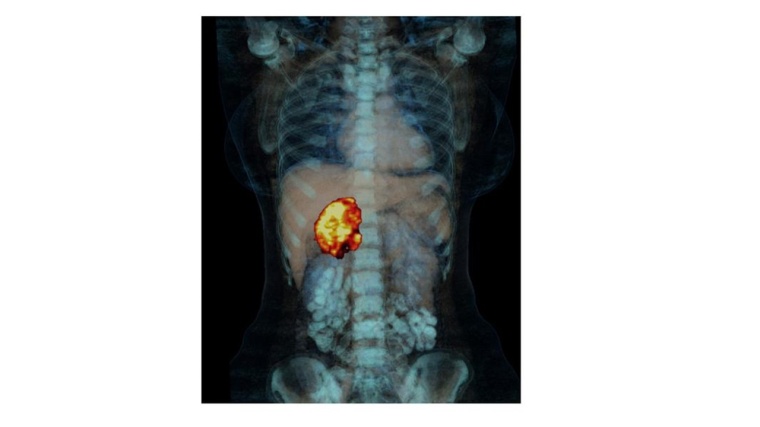

Eine Studie belegt: nicht alle Patienten mit Nebennierenkarzinom benötigen nach einer kompletten Tumorentfernung die bisherige Standardtherapie Mitotane.

In der klinischen Studie ADIUVO konnten die Professoren für Innere Medizin und Endokrinologie Martin Fassnacht (Universität Würzburg) und Massimo Terzolo (Universität Turin, Italien) mit ihren Teams zeigen, dass nicht alle Patienten mit Nebennierenkarzinom nach einer kompletten Tumorentfernung die bisherige Standardtherapie Mitotane benötigen.